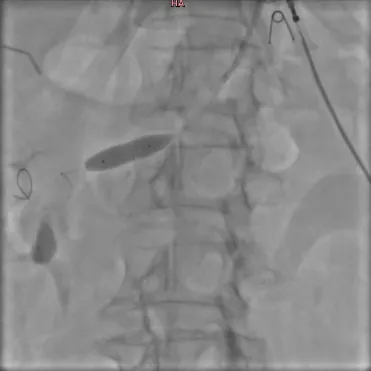

2. Имплантация стента